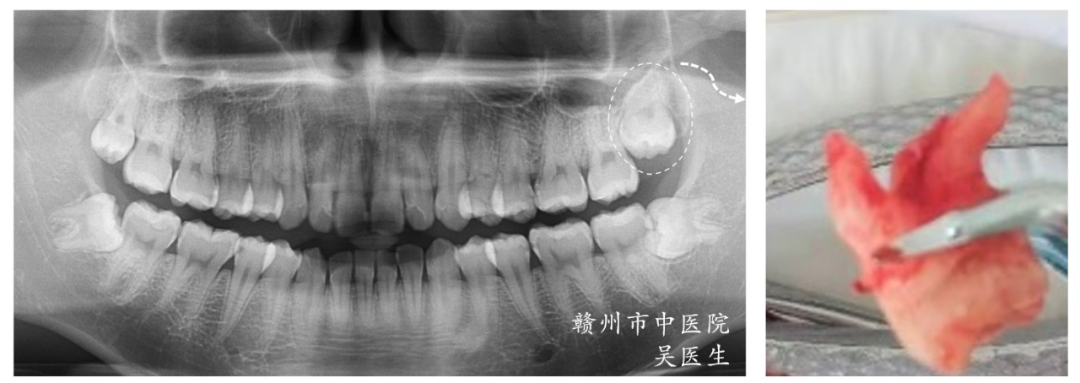

3.CT在拔牙治疗中的应用

CT检查能直观分辨患牙的牙根数量、牙根形态、是否带钩,在牙齿拔除等方面,让医生在术前有更直观的判断,以获得更精准的手术效果。